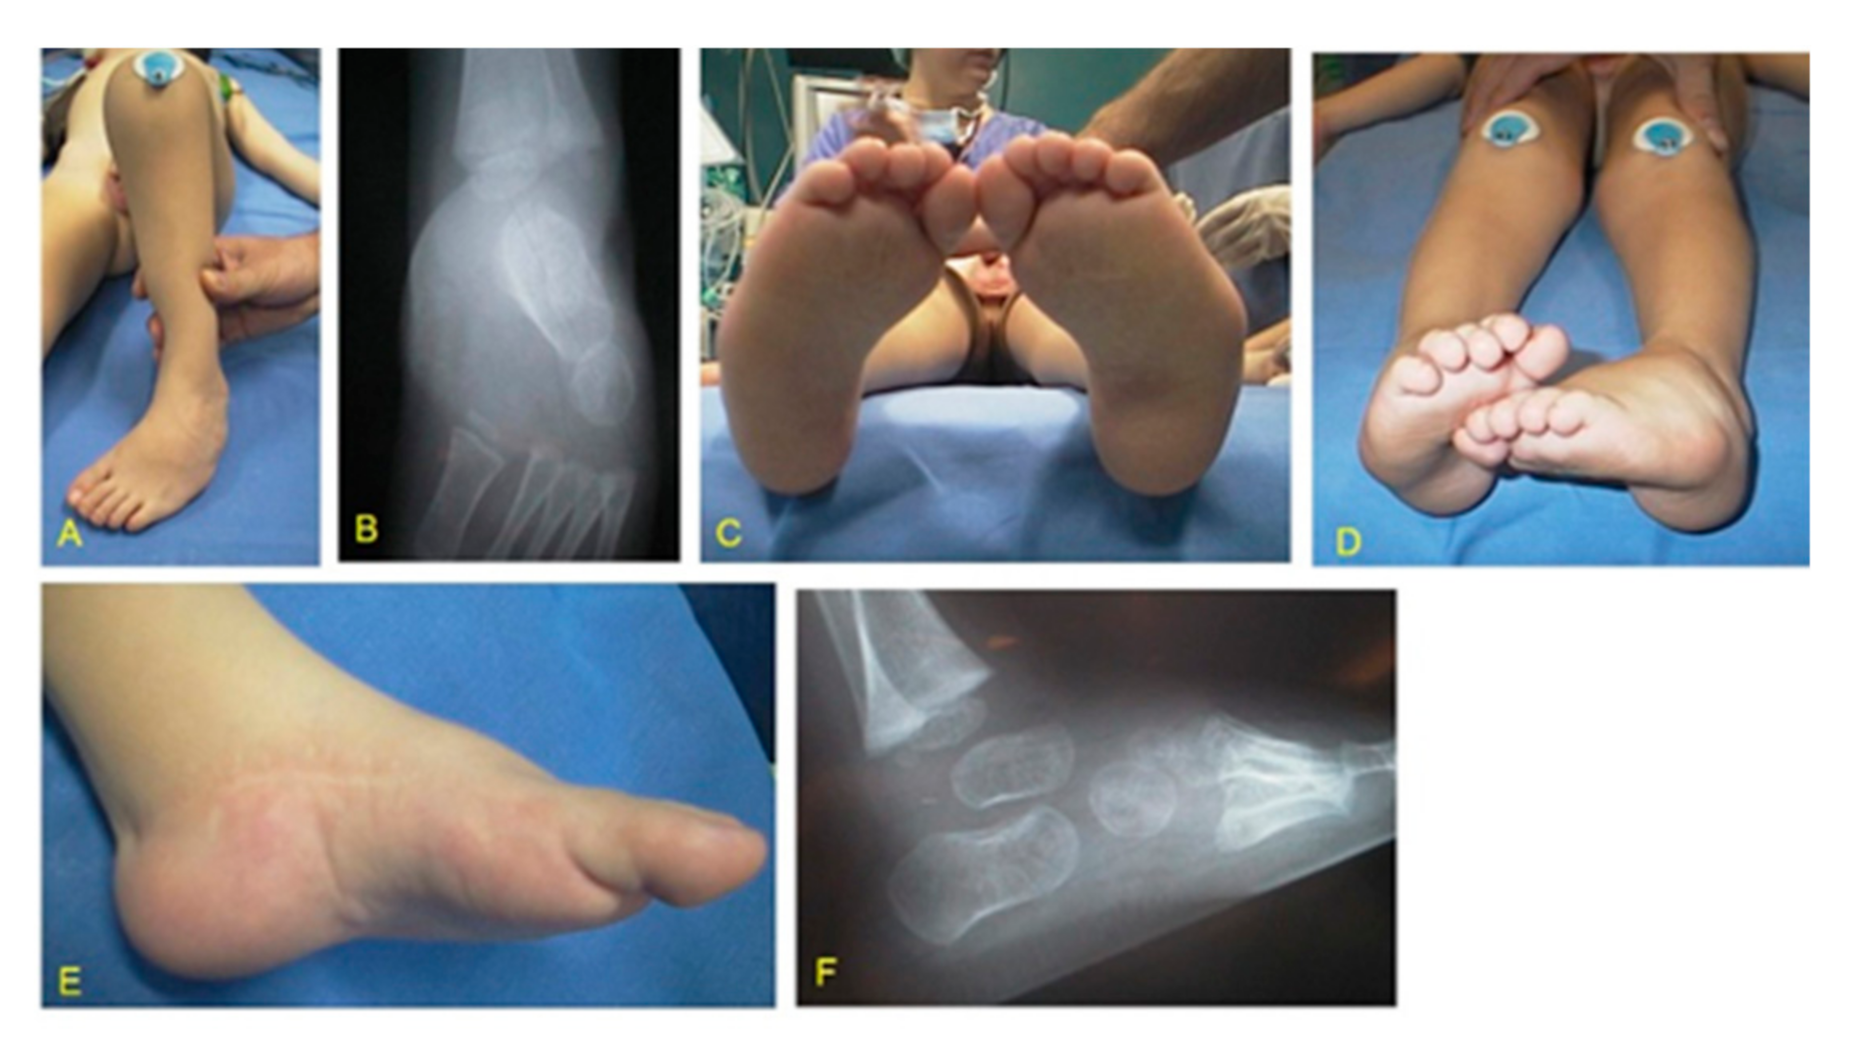

It is a congenital deformity characterized by plantar flexin (equinus) and inversion (varus) of the ankle so that dorsiflexion of the foot is limited; and unlike normal babies, the dorsum of the foot can not be made to touch the front of shin.

Club foot (Talepes equinovarus) is a combination of abnormalities of bony architecture and soft tissue. Fore foot adduction and supination, heel varus, ankle equines and medial deviation of the entire foot are 4 abnormal features presented with club foot.

Congenital talipes equinovarus is a grotesque looking deformity of the foot. Five classical primary deformities are seen and in response to this, secondary deformities develop. The primary and secondary deformities together form the club foot complex.